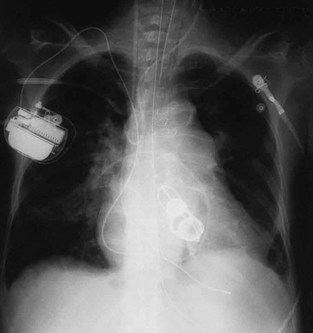

The ability of X-rays to penetrate matter depends on density, and so an X-ray image can reveal very detailed density information. Figure 24.20 shows an example of the simplest type of X-ray image, an X-ray shadow on film. The amount of information in a simple X-ray image is impressive, but more

sophisticated techniques, such as CT scans, can reveal three-dimensional information with details smaller than a millimeter.

Figure 24.20 This shadow X-ray image shows many interesting features, such as artificial heart valves, a pacemaker, and the wires used to close the sternum. (credit: P. P.

Urone)